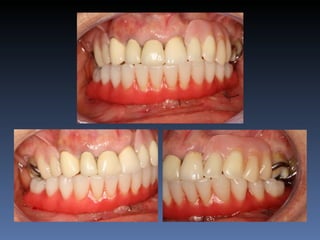

Maurício Zanetti

Idade – 47 anos

Sexo – Masculino

Raça – Caucasiana

ASA – II

Data- 25-04-2012

Diagnóstico: Desdentado parcial

pré-maxila.

Plano de tratamento: Reabilitação pré-maxila com

instalação de 2 implantes endo-ósseos (1.1,.2.2), para

reabilitação protética fixa.